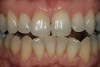

Figure 9  A reasonable match was obtained from about 8 weeks of single-tooth bleaching. Often patients discontinue treatment when the single tooth is no longer a mismatch, even if the outcome is not ideal.

Figure 9